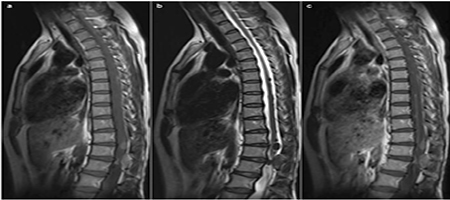

9. Neurocutaneous melanosis with intraspinal malignant melanoma in adults-an extremely rare clinical entity: A case report with review of literature

Dongkang Liu, Yujun Wei, James Wang, Guihuai Wang

临床转化神经科学    2016, 2 (4): 236-240.   DOI: 10.18679/CN11-6030/R.2016.039

摘要459)      PDF (3124KB)(487)

Objective: Neurocutaneous melanosis (NCM) in adult patients was rare, and few cases had been reported. In this report, we summarized the features of NCM in adult patients for providing useful information about this rare clinical entity.

Methods: In this report, we present a case of a 41-year-old woman, who was eventually diagnosed with NCM with intraspinal malignant melanoma. The clinical features, treatments, and prognosis of cases of NCM in adults were thoroughly reviewed and discussed.

Results: A 41-year-old woman was eventually diagnosed with NCM with intraspinal malignant melanoma. The post-operative course was uneventful and her symptoms significantly improved (VAS: 3 points). However, she developed symptoms of intracranial hypertension and deteriorated rapidly after 11 months of operation, and died 1 month later. To date, only 15 cases of NCM in adults have been reported in the English literature. Analyses showed that the average age was 33.8 years (range 19-65 years), and 11 patients (68.8%) were between 20 and 40 years. A slight male predominance (M:F/11:5) was found. For the 12 cases which detailed follow-up information was available, 9 patients (75%) died, with a survival time ranging from 1 day to 29 months post-operation. Death occurred within the first month of operation in 6 cases (46.2%). The median survival time was 3 months.

Conclusions: We presented a rare case of NCM with intraspinal malignant melanoma in an adult patient. Although rare, this clinical entity causes significant mortality and has poor prognosis.

图表 | 参考文献 | 相关文章 | 多维度评价